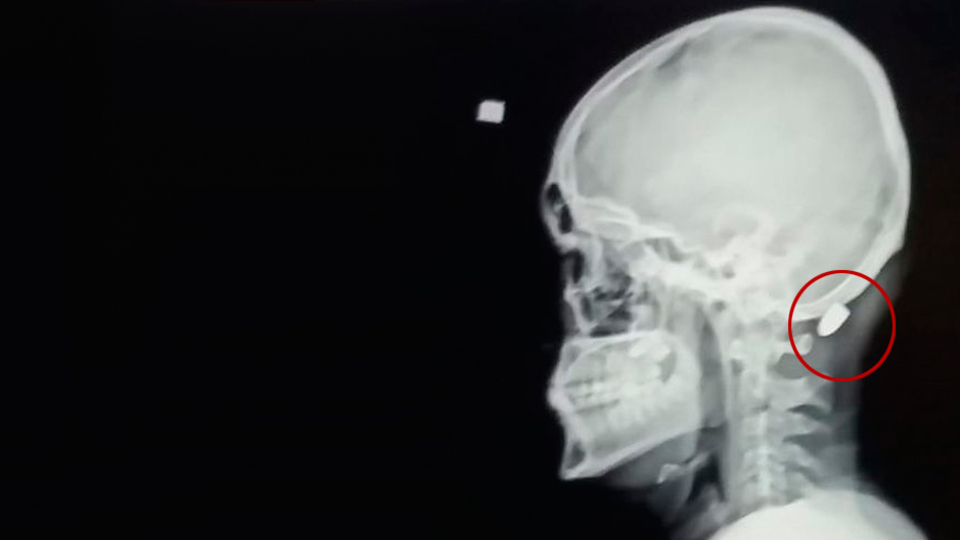

Trabzon'un Vakfıkebir ilçesine bağlı Karadağ Yaylası'nda gezmeye çıkan Ali Kuleyin (18), henüz kim tarafından ateşlendiği bilinmeyen tabancadan çıkan kurşun ile vuruldu. Ensesine isabet eden kurşun ameliyatla çıkarılan genç, tedavisinin ardından taburcu edildi

DHA'nın haberine göre, olay, dün saat 14.30 sıralarında Karadağ Yaylası'nda meydana geldi. Ali Kuleyin yaylada gezindiği sırada ensesinde acı hissetti. Genç, ensesini arkadaşlarına gösterdi. Kuleyin'in ensesinde mermi çekirdeği olduğunu fark eden arkadaşları, durumu sağlık ekiplerine haber verdi. Gelen sağlık ekiplerince ilk müdahalesi yapılan Kuleyin, ambulansla Vakfıkebir Devlet Hastanesi'ne kaldırıldı. Mermi, ameliyatla çıkarıldı. Sağlık durumunun iyi olduğu bildirirken Ali Kuleyin, tedavisinin ardından taburcu edildi.